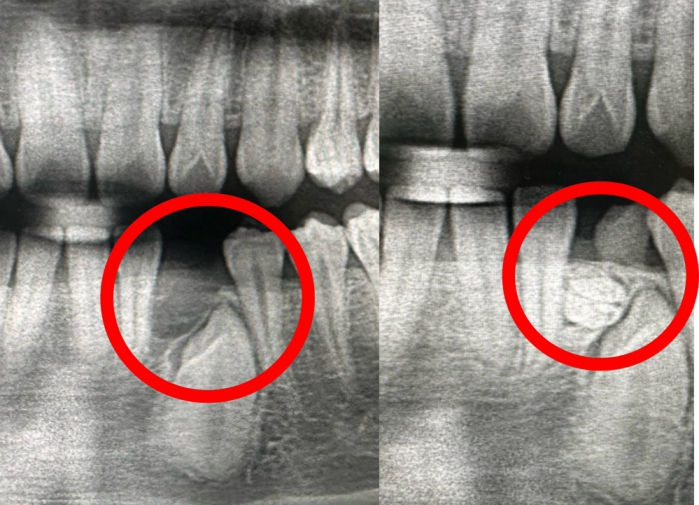

【記者林獻元台中報導】一名高中生大樹(化名),因乳牙遲遲未脫落,前往衛生福利部豐原醫院醫院求診,成長過程中完全沒有疼痛或不適感,原以為只是換牙較慢,沒想到透過X光檢查,竟在乳牙下方發現有約10顆牙齒組成的「齒瘤」,牙科主任朱晃照表示,這類情況相當罕見。朱晃照指出,齒瘤是口腔顎骨中最常見的良性齒源性腫瘤之一,但其實屬於牙齒發育異常形成的錯構瘤,內含牙釉質、牙本質與牙髓等組織,可能呈現為一顆顆迷你牙齒(混合性齒瘤),也可能是不規則鈣化團塊(複合性齒瘤),而本案例正是典型的多顆牙齒型態。

豐原醫院牙科主任朱晃照說明,根據研究指出齒瘤整體發生率約在0.2%至1%左右,齒瘤最容易被忽略的原因在於幾乎沒有症狀,齒瘤常見於青少年階段,尤其在換牙期間更需特別留意,不少患者直到恆牙遲遲未長出、牙齒排列異常,甚至準備矯正時才被發現,實際上齒瘤會阻擋牙齒正常萌發路徑,長期下來可能導致牙齒歪斜、咬合不正,甚至影響顎骨發育與臉型。朱晃照提到,若出現乳牙遲遲未脫落、恆牙未萌發、牙齦局部隆起,或牙齒排列突然出現異常等情況,都可能是齒瘤阻擋牙齒生長的徵兆。

朱晃照表示,在治療上,口腔顎面外科手術是關鍵,透過數位X光與3D影像定位,可精準判斷齒瘤位置與範圍,多數情況可採微創方式完整移除,傷口小、恢復期短,安全性高,術後再依牙齒生長情況評估是否需要矯正,多數患者都能順利恢復正常齒列。